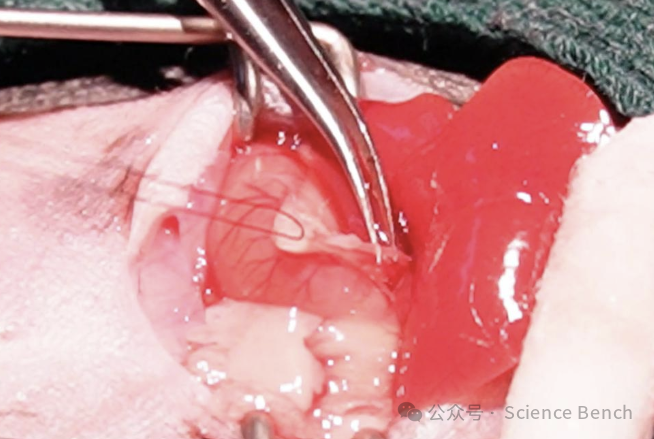

步骤:麻醉小鼠后,开腹找到胆总管,进行双重结扎并在中间剪断,然后关腹。假手术组只分离胆总管但不结扎不剪断。

• 用手术剪逐层剪开皮肤及肌肉等组织;将肝叶、胃及部分肠管轻轻拨开;

• 继续向下可见胆管常附着于一小段肠管之上;使用缝合线轻轻地挑起胆管,此时可以清晰地看到透明胆管;轻柔钝性游离一小段胆管;埋置2条手术缝合线并分别打手术结;线头留取长度不宜过短,约0.5cm即可;并从两个结扎处的中间将胆管剪短;确认腹腔内无脏器损伤或出血后,以棉签轻轻复位肝叶、胃及肠管。